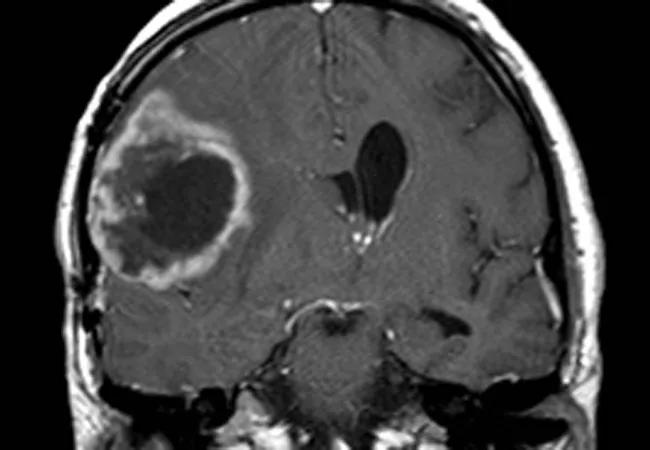

Vasorin: The Achilles’ Heel of Glioma Stem Cells

Hypoxic induction of vasorin regulates Notch1 turnover

CSCs are elusive and difficult to destroy, especially CSCs that reside in hypoxic areas of tumors where radiation and chemotherapy are less effective. With this in mind, Dr. Yu and colleagues recently undertook an investigation to learn more about the molecular mechanisms of CSCs in hypoxic regions of glioma tumors.

The team first studied human glioma samples from a tissue database to identify candidate proteins that might be involved in this pathway. They found that a protein called vasorin — known to be induced in hypoxic settings — was abundant in patients with aggressive brain cancers who had poorer survival.

Next they studied vasorin in cell culture to determine how it affects glioblastoma progression. Under normal conditions, an adaptor protein binds to and inhibits the pro-cancer Notch pathway (important for cell proliferation, differentiation and survival). They found that in a hypoxic environment, however, the abnormally abundant vasorin instead binds to and switches on the Notch signaling pathway in glioblastoma stem cells, leading to unchecked tumor growth.

“I think with vasorin we found an Achilles’ heel for the glioma stem cells in these hypoxic areas,” Dr. Yu says.